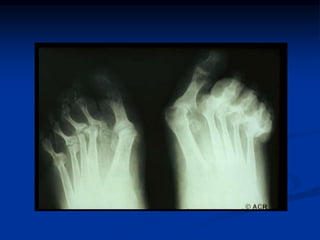

 Small joints of hand and feet are typically involved.

 MCP and PIP joints of hands & MTP of feet 90%

Radiographic Features

 Peri-articular osteopenia

 Uniform symmetric joint space narrowing

 Marginal subchondral erosions

 Joint Subluxations

 Joint destruction

 Collapse